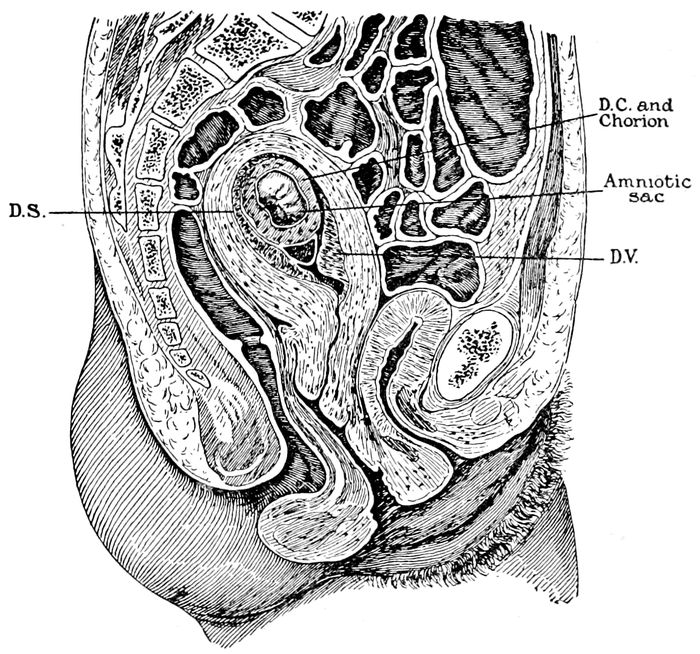

Fig. 16.—Diagram illustrating relations of structures of the human uterus at the end of the seventh week of pregnancy. (American Text Book.)